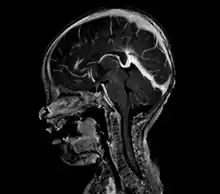

vein of Galen malformation

A cerebral AVM diagnosis is established by neuroimaging studies after a complete neurological and physical examination.[5][12] Three main techniques are used to visualize the brain and search for an AVM: computed tomography (CT), magnetic resonance imaging (MRI), and cerebral angiography.[12] A CT scan of the head is usually performed first when the subject is symptomatic. It can suggest the approximate site of the bleed.[3] MRI is more sensitive than CT in the diagnosis, and provides better information about the exact location of the malformation.[12] More detailed pictures of the tangle of blood vessels that compose an AVM can be obtained by using radioactive agents injected into the blood stream. If a CT is used in conjunctiangiogram, this is called a computerized tomography angiogram; while, if MRI is used it is called magnetic resonance angiogram.[3][12] The best images of a cerebral AVM are obtained through cerebral angiography. This procedure involves using a catheter, threaded through an artery up to the head, to deliver a contrast agent into the AVM. As the contrast agent flows through the AVM structure, a sequence of X-ray images are obtained.[12]